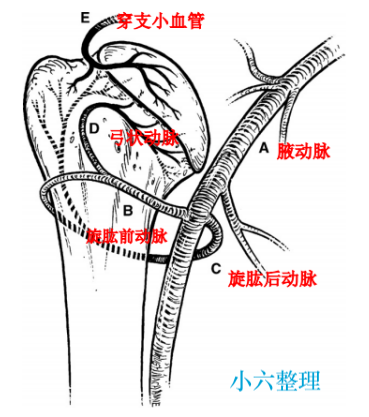

血供